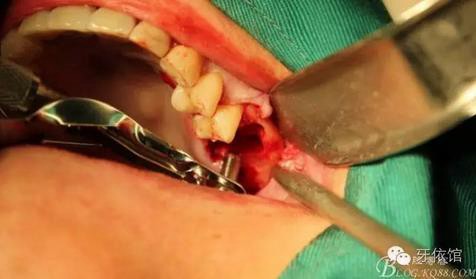

上6分根

依次拔除3個根